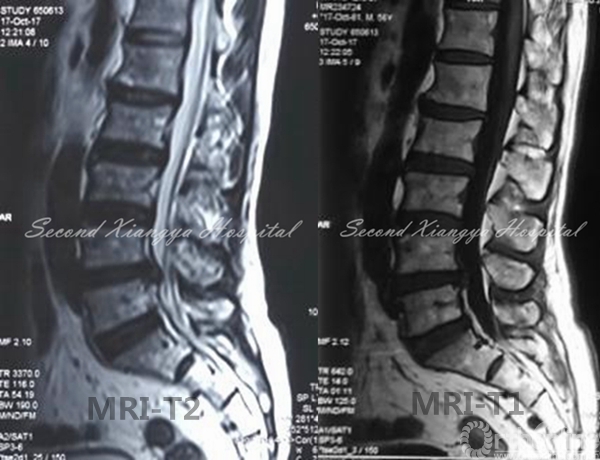

MRI:L4/5椎间盘右侧突出,非游离,无钙化,伴侧隐窝狭窄。

MRI-T2、MRI-T1